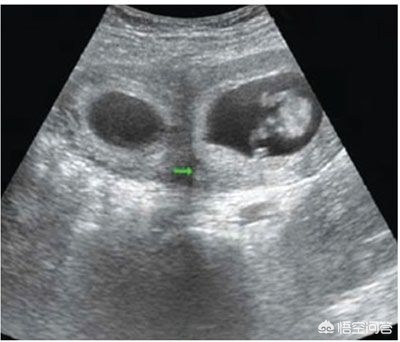

我们知道,在孕早期,妊娠6~7周超声检查就可以观察到胎囊的存在,7~8周可以看到胎心搏动,超声检查正是通过观察胎囊和胎心来确定妊娠是单胎还是多胎。

如上所述,在孕早期,妊娠6~7周超声检查可以观察到胎囊的存在,7~8周可以看到胎心搏动,超声检查正是通过观察胎囊和胎心来确定妊娠是单胎还是多胎。

如果在之后的超声检查中,观察到原本存在的胚胎或胎儿数量减少,就可以诊断为胞胎消没综合征。

有一些“压扁胎”可以通过超声检查观察到。